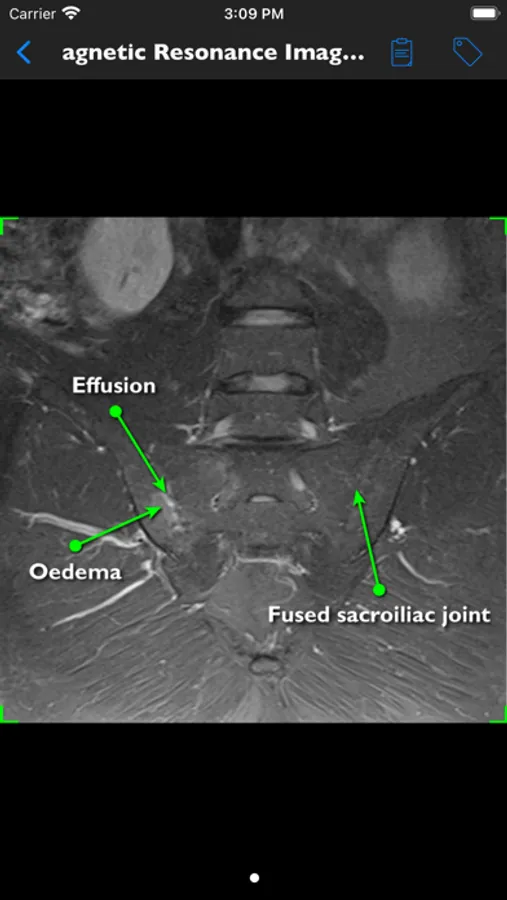

• detailed information on history, physical examination, assessment tools (printable), differential diagnosis, laboratory studies, histology and a medical imaging library of over 400 Xrays, CTs and MRIs